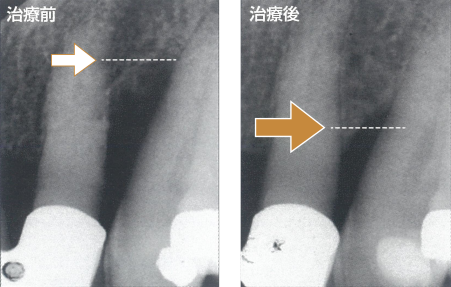

エムドゲイン®ゲル使用例の

12ヶ月後の経過

エムドゲイン®ゲル使用例の

12ヶ月後の経過

損なわれた骨が回復し、長期にわたって維持されます。

損なわれた骨が回復し、長期にわたって維持されます。